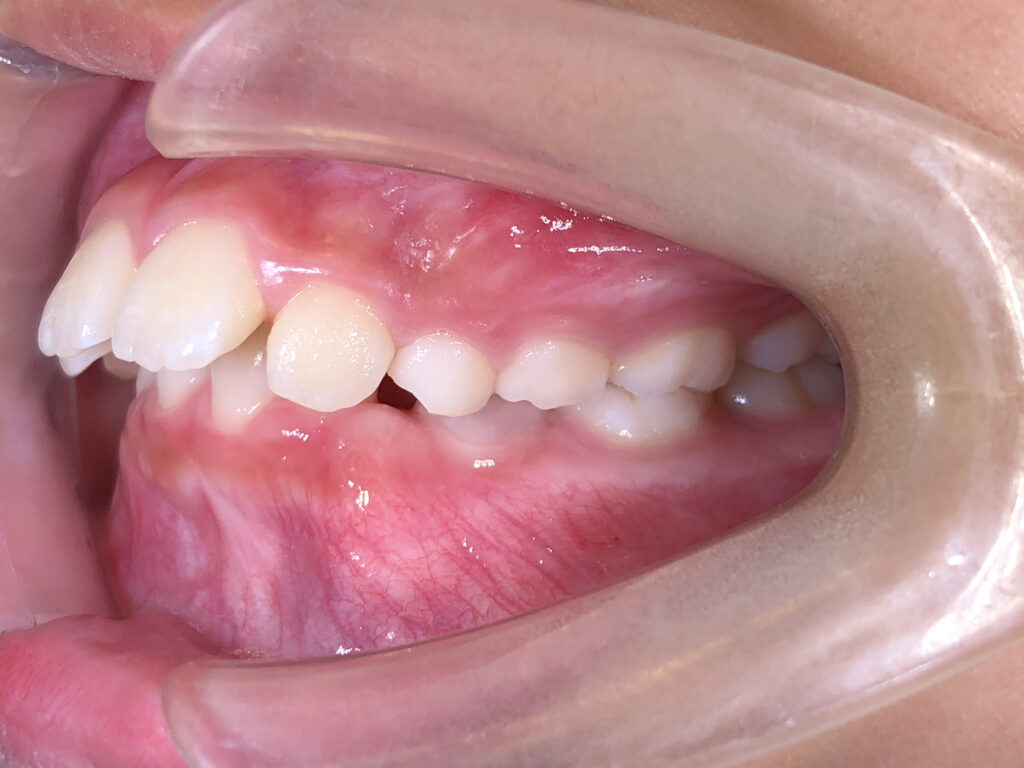

左側

治療前